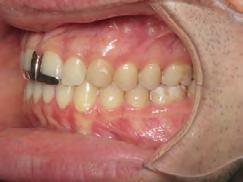

4). Archwires were upgraded incrementally into 19 x 25 SS. Once the bite was completely closed, the patient was referred to the myofunctional therapist to begin treatment. Eight sessions of myofunctional exercises were performed, focusing on muscle building, toning, synchronicity and awareness. Improvement in correct chewing, swallowing and resting postures of the lip and tongue were addressed. All appliances were removed 21 months after initial insertion (Figure 5), and the patient was referred to a re-

storative dentist for veneers on the maxillary central incisors; the patient opted for gold veneers (Figure 6). Clear removable retainers were inserted with a fixed mandibular retainer canine-to-canine.

Treatment Results

The patient finished with Class I occlusion, ideal overbite and overjet. The arches are co-

Figure 5. Final records.

ordinated, lateral open bite closed and occlusal cants leveled. From the frontal cephalometric tracings, maxillary width increased from 58 mm to 69 mm. From the lateral cephalometric tracing, the incisor angulations remained unchanged. The final report from the myofunctional therapist indicated the patient eliminated the bilateral posterior tongue-thrust swallowing pattern with saliva, liquid and solid swallows. Correct swallowing mechanics were demonstrated while sipping/gulping liquids from a cup. His day and nighttime tongue-resting postures were reported to be on his incisive papilla, with lateral margins lightly suctioned into the upper arch. Lips were closed and competent diurnally and nocturnally.